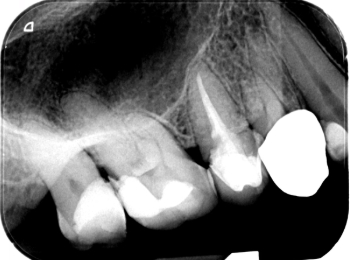

Röntgen Krone distal

25: apikal aufgehellt, Krone distal undicht, WF reicht nicht bis ins untere Drittel.

26 und 27 nicht erhaltungswürdig, vertikaler Knocheneinbruch.